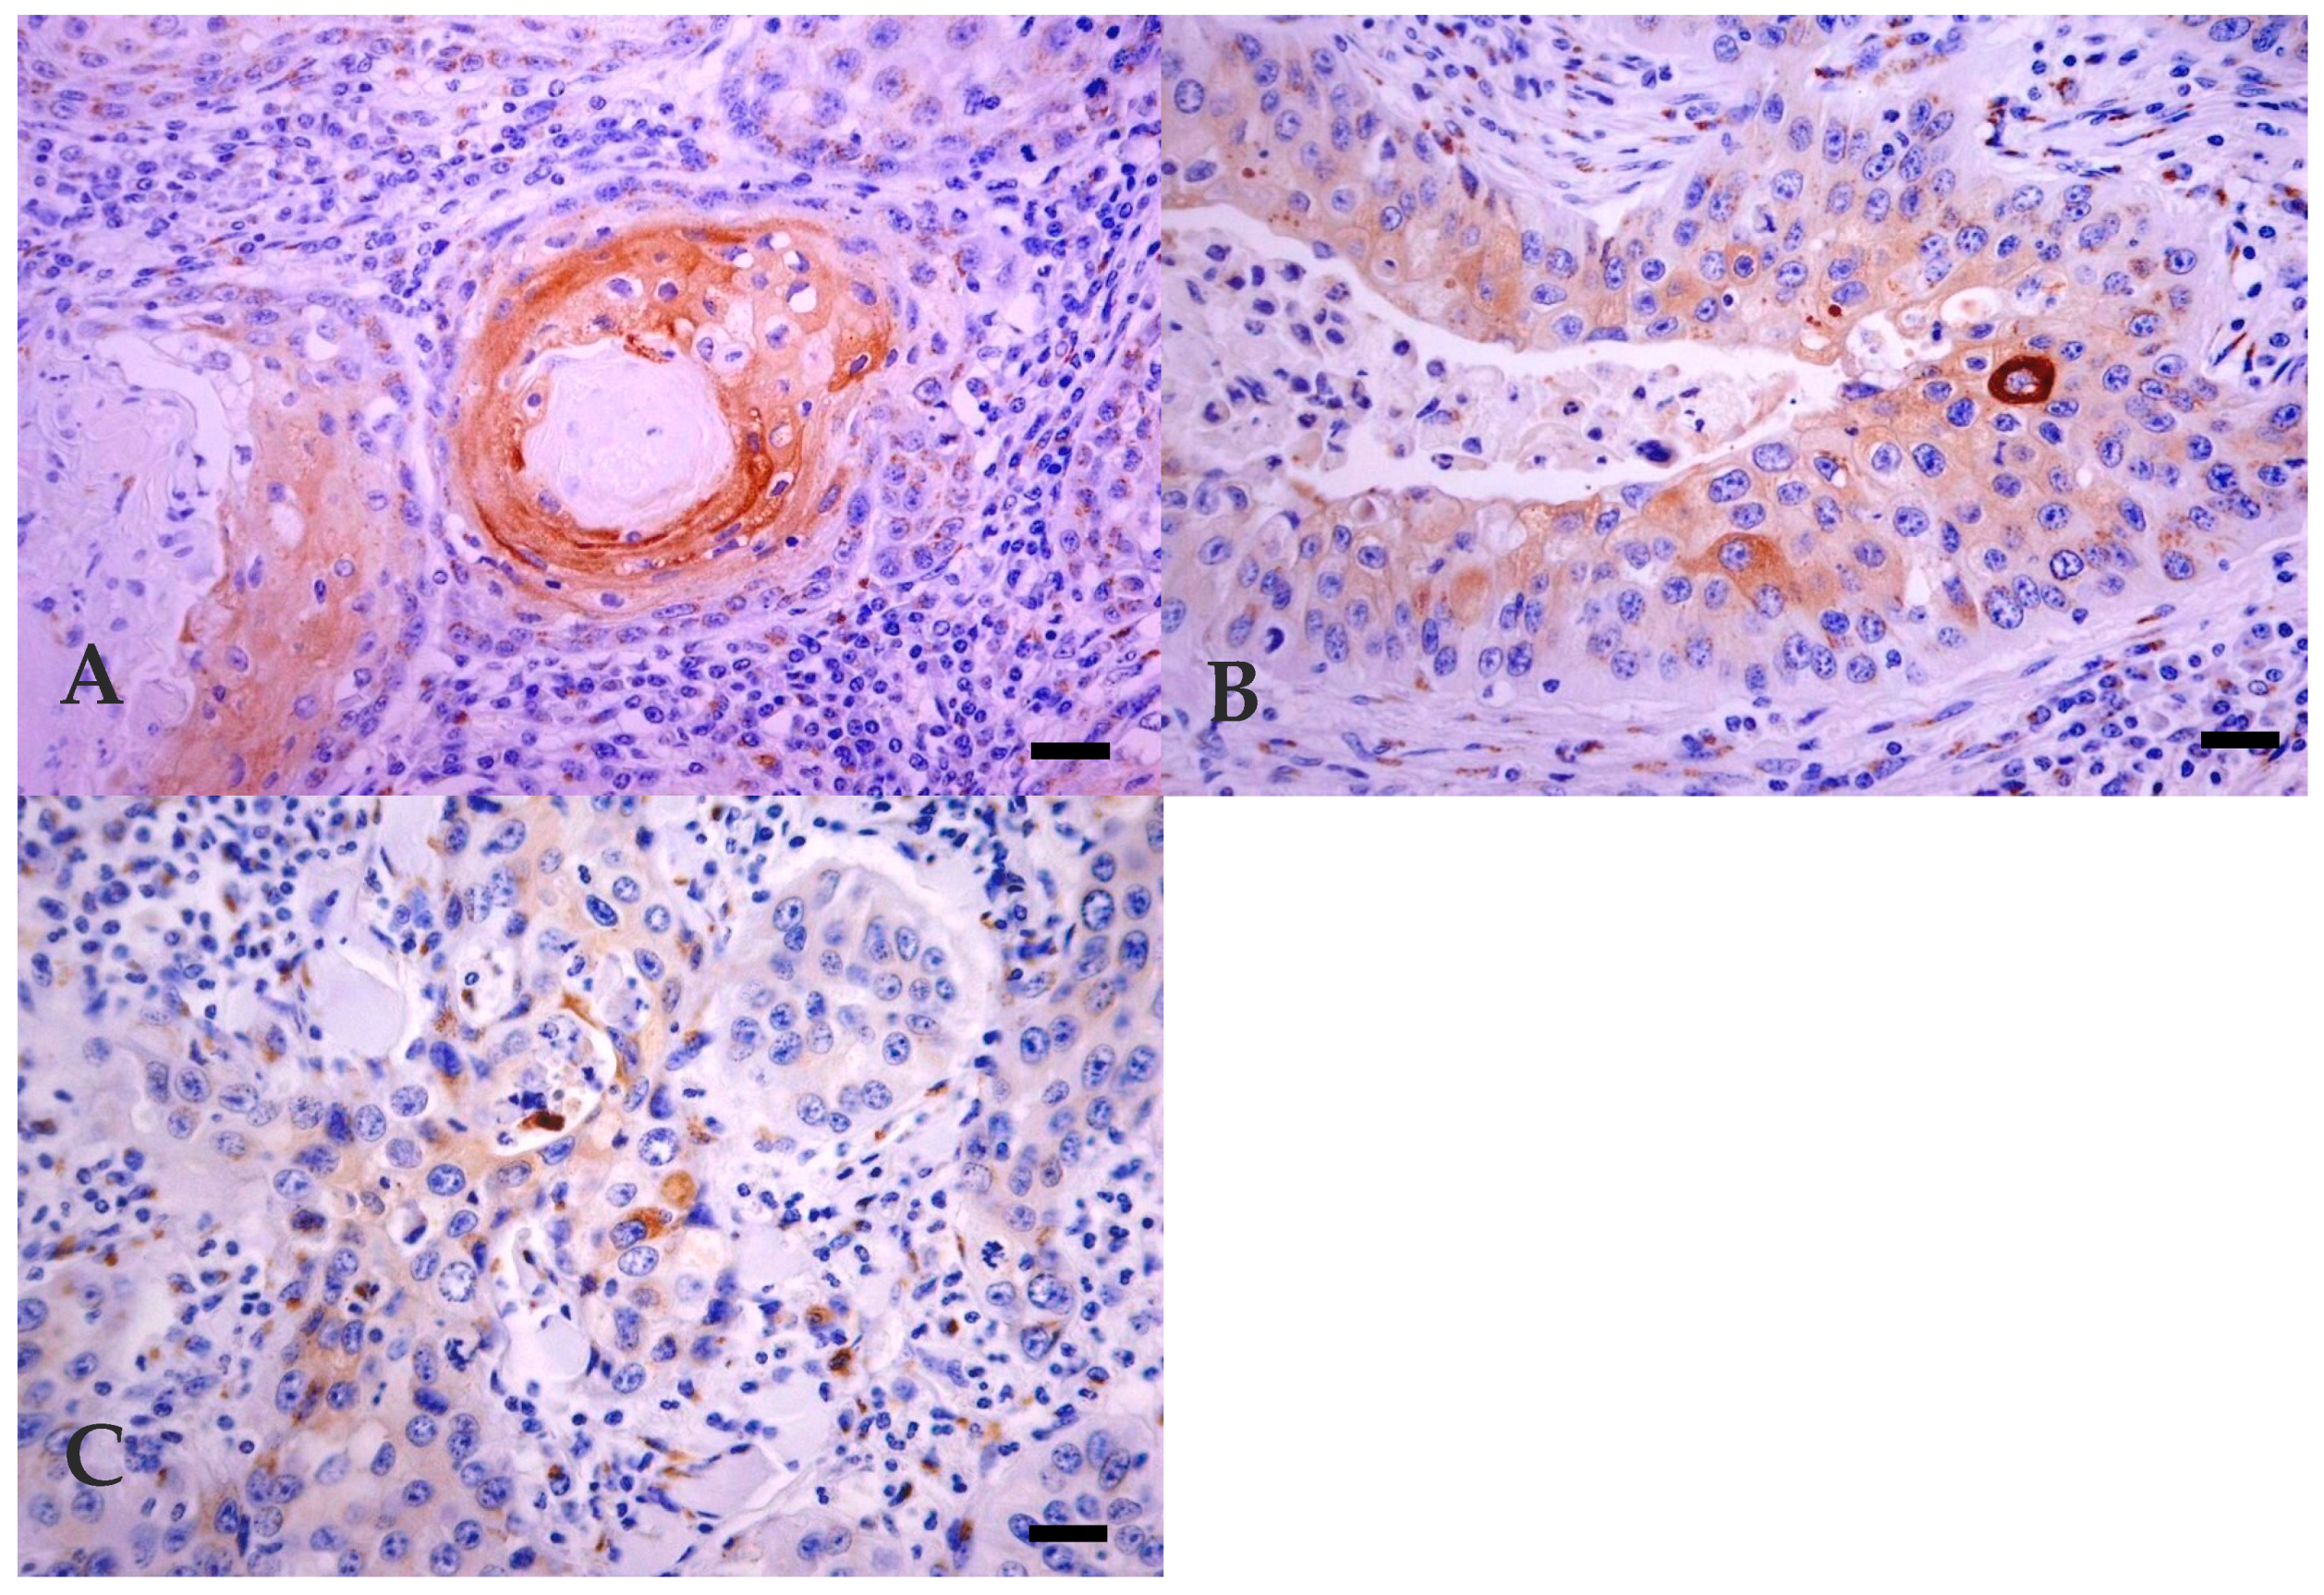

3.3. Immunohistochemistry

| Degree of Differentiation | |||

| Keratinisation Degree | Pattern | Cellular Phenotype | |

| Well Differentiated | Numerous large keratin pearls | Large islands, trabeculae or cords formation, with central squamous differentiation | Small basal-like cells at the periphery and well-differentiated keratinocytes, with homogenous eosinophilic cytoplasm and clear intercellular bridges in the central areas |

| Moderately Differentiated | Small to medium sized keratin pearls | Smaller islands and squamous differentiation, acantolytic cysts | Increased number of poorly differentiated cells |

| Poorly Differentiated | Individual cell keratinisation | Few small sized islands, poor cellular differentiation | Predominance of areas with more pleomorphic and atypical cells |

| Animal * | Age (Year) | Localization of Tumour | Histological Classification ** | Invasiveness ‡ | Mitosis § | Immunohistochemistry † | |||

|---|---|---|---|---|---|---|---|---|---|

| MNF 116 | LP 34 | Involucrin | Filaggrin | ||||||

| 1 | 6 | Third eyelid | WD | MI | 0–20 | +++ | +++ | + | +++ |

| 2 | 5 | Eyelid | WD | MI | 0-20 | +++ | ++ | + | ++++ |

| 3 | 8 | Third eyelid | WD | NI | >60 | ++++ | + | + | ++++ |

| 4 | 4 | Eyelid | WD | NI | 30–60 | ++++ | ++ | + | ++++ |

| 5 | 10 | Third eyelid | WD | VI | 0–20 | ++++ | ++++ | + | ++ |

| 6 | 10 | Whole ocular region | WD | VI | 0–20 | +++ | − | + | − |

| 7 | 8 | Eyelid | WD | VI | 0–20 | ++++ | ++ | + | + |

| 8 | 8 | Eyelid | WD | NI | 0–20 | ++++ | + | + | + |

| 9 | 7 | Third eyelid | WD | VI | 0–20 | ++++ | +++ | + | +++ |

| 10 | 9 | Third eyelid | MD | MI | >60 | ++++ | + | + | ++++ |

| 11 | 8 | Whole ocular region | MD | VI | 0–20 | ++++ | ++++ | + | + |

| 12 | 8 | Eyelid | MD | VI | 0–20 | ++++ | − | + | − |

| 13 | 4 | Third eyelid | MD | VI | 0–20 | ++++ | +++ | + | − |

| 14 | 9 | Eyelid | MD | VI | 0–20 | ++++ | + | + | − |

| 15 | 6 | Third eyelid | PD | VI | 30–60 | ++++ | − | + | ++++ |

| 16 | 7 | Whole ocular region | PD | VI | 30–60 | ++++ | + | + | + |

| 17 | Eyelid | PD | VI | 0–20 | ++++ | + | − | ++ | |

| 18 | 8 | Eyelid | PD | VI | >60 | ++++ | + | + | + |

| 19 | 10 | Third eyelid | PD | VI | 0–20 | ++++ | ++ | + | − |